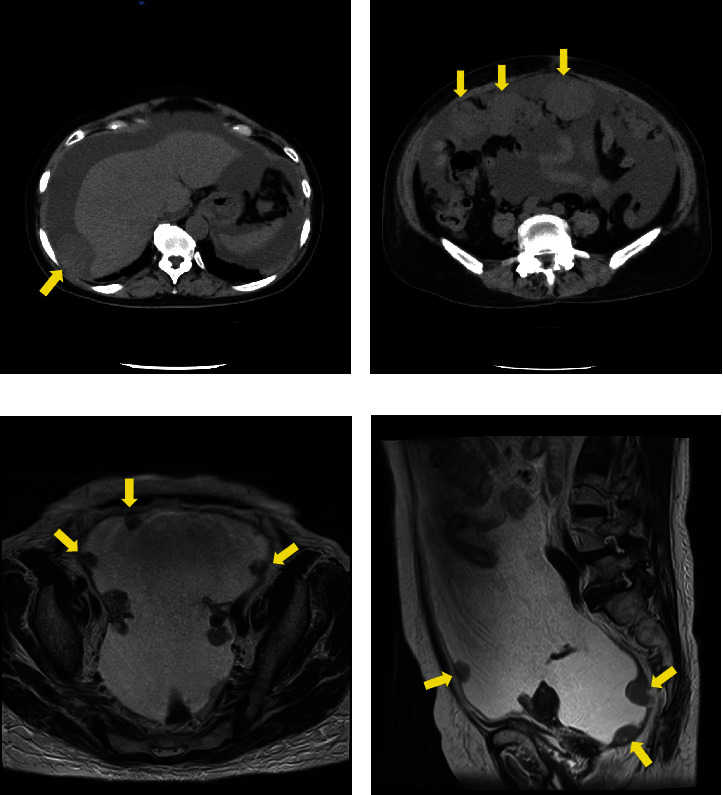

在本病例中,一名 66 岁的女性患者以腹胀为主诉。计算机断层扫描和磁共振成像显示卵巢没有增大,也没有明显的原发病灶;但观察到大量腹水和腹膜播散性结节。腹水细胞学显示为腺癌,免疫组化结果显示为浆液性癌。术前化疗后,患者接受了疑似 IIIC 期原发性腹膜癌的肿瘤缩小手术。术后组织病理学显示,癌细胞主要由高级别浆液性癌(HGSC)和肉瘤组成。此外,在左侧输卵管的缘膜上还发现了输卵管浆液性上皮内癌(STIC)。最近有文献指出,大多数腹膜癌病例都是源自输卵管纤毛缘的癌转移或扩散。这是一例罕见的伴有STIC的腹膜癌,报告该病例有助于更好地了解该疾病的特征和可能的治疗方法。

In this case, a 66-year-old female patient presented with the chief complaint of abdominal distention. Computed tomography and magnetic resonance imaging revealed no enlarged ovaries or obvious primary lesions; however, massive ascites and peritoneal disseminated nodules were observed. Ascites cytology revealed adenocarcinoma and immunohistochemical findings suggested serous carcinoma. The patient then underwent tumor reduction surgery after preoperative chemotherapy for suspected Stage IIIC primary peritoneal carcinoma. Postoperative histopathology revealed carcinoma consisting mainly of high-grade serous carcinoma (HGSC) and sarcoma. In addition, serous intraepithelial carcinoma (STIC) of the fallopian tube was observed in the fimbriae of the left fallopian tube. Recently, it has been noted in the literature that most cases of peritoneal carcinoma are metastases or dissemination of carcinoma originating from the fimbriae of the fallopian tube. This is a rare case of peritoneal carcinosarcoma with STIC, and its report leads to a better understanding of the disease's features and possible therapeutic approaches.